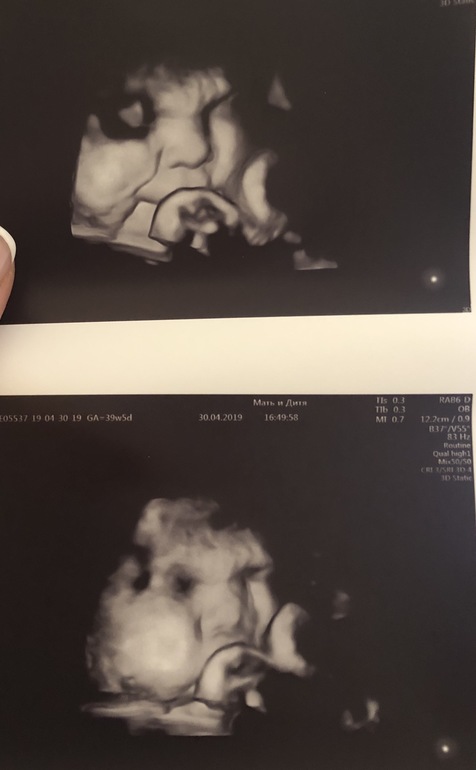

Узистка умудрилась сфоткать лицо) и хоть и не люблю я 3д, оставлю это здесь

Вес намерила 3400 против 4 кг, которые ожидала я. По всем параметрам доношен. Маловодие - сказали, норма для этого срока.